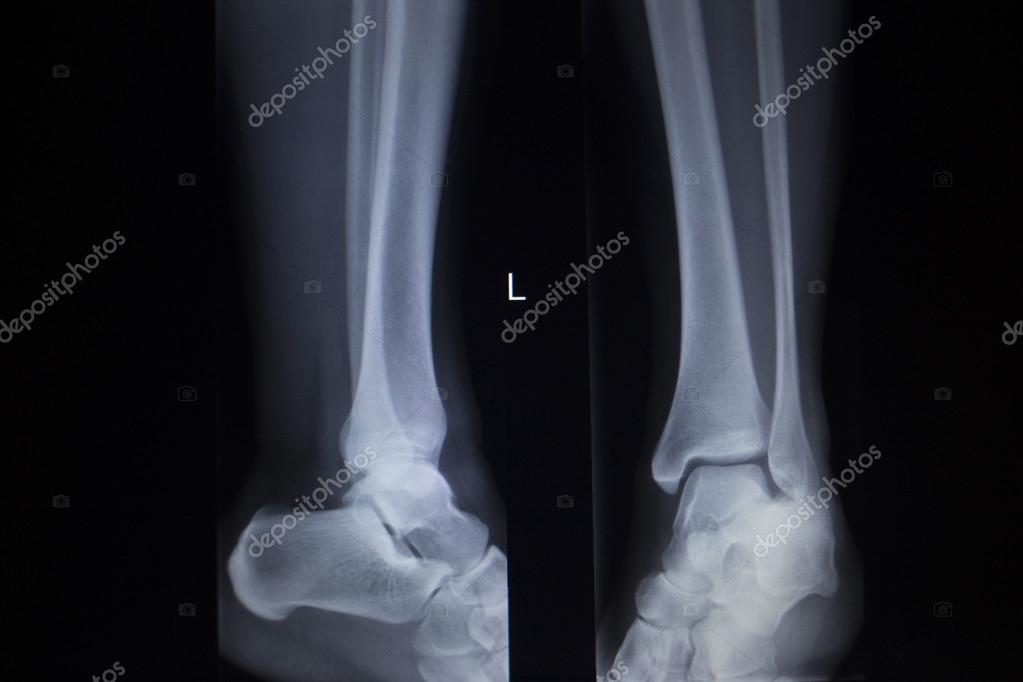

Переломы костей голени (большеберцовой и малоберцовой) и костей заднего отдела стопы (таранной и пяточной) приводят к возникновению деформирующего артроза голеностопного и подтаранного суставов. Это заболевание возникает также вследствие дегенеративно-дистрофических изменений, вызванных ревматическими и неврологическими болезнями, пожилым возрастом пациента.

Данная болезнь характеризуется истончением и гибелью суставного хряща, образованием костных выростов – «шипов», деформацией нижней конечности. Пациента беспокоят постоянные боли, отеки области голени, ограничение амплитуды движений в голеностопном суставе, снижение опорности нижней конечности. Отеки и деформация конечности приводят к постоянным неудобствам с выбором и ношением обуви. Данное заболевание характеризуется необратимостью изменений, поэтому консервативные методы лечения обладают непродолжительным эффектом только на ранних стадиях заболевания (обычно I-II), с наступлением III стадии они становятся неэффективными и даже ускоряют разрушение сустава.

Остеоартроз приводит к деформации сустава различной степени выраженности. В самом начале заболевания этот симптом можно выявить только при рентгенологическом исследовании или при магниторезонансной томографии. Если заболевание будет выявлено на ранних стадиях своего развития, то развитие деформации можно предотвратить или значительно замедлить. Вот почему важно своевременное обращение к врачу!

Деформирующий посттравматический артроз голеностопного сустава

В большинстве случаев деформирующий артроз является следствием перенесённой тяжёлой травмы одной или нескольких его анатомических составляющих — наружной и внутренней лодыжки, большеберцовой кости, таранной кости. В результате травмы поверхность костей, входящих в сустав, становиться неровной, что приводит к нарушению скольжения суставных поверхностей и их дополнительной травматизации при движении.

Проявления деформирующего артроза разнообразны. Боли в области голеностопного сустава и мышц голени, опухание сустава, ограничение подвижности в нём, нарушение походки, ограничение ходьбы на длинные дистанции — вот лишь неполный список страданий, которые испытывает пациент с подобным заболеванием.